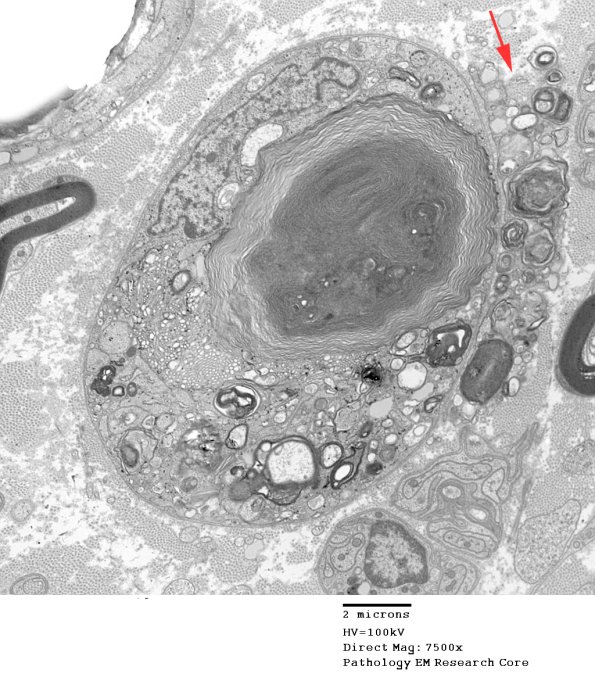

A central area of myelin may be the nidus for the lipidic debris seen in inactive chronic changes. At the right margin there is an extraneous cell (arrow), surely a macrophage, removing debris from the adjacent Schwann cell. This process is also shown in the atlas macrophage PNS section.